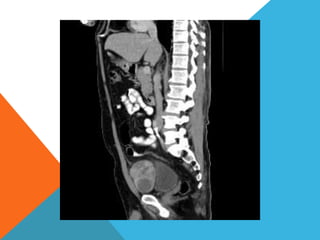

El paciente presentó síntomas de sangrado digestivo y pérdida de peso. Exámenes revelaron gastritis crónica asociada a H. pylori. Un tumor fue descubierto en una colonoscopia normal. La cirugía removió un tumor fibroide solitario, una rara neoplasia mesenquimal que usualmente crece lento y tiene bajo potencial de malignidad. El pronóstico después de la remoción quirúrgica es generalmente bueno.